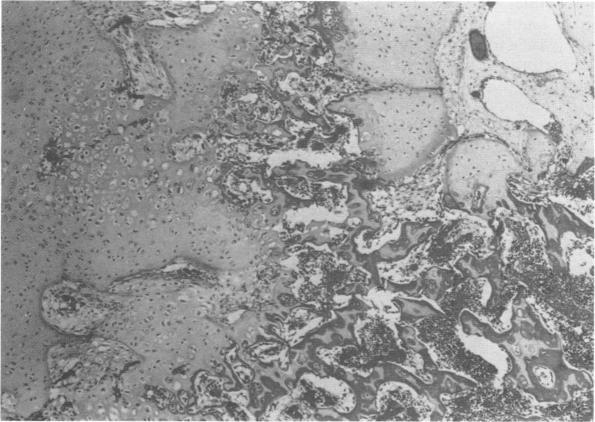

https://cdn.ncbi.nlm.nih.gov/pmc/blobs/c84b/1015608/5e2f80faa2f8/jmedgene00055-0059-a.jpg